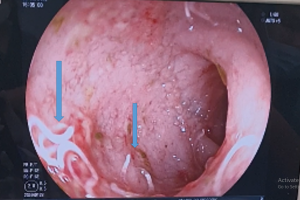

Vừa qua Bệnh viện Nhi Đồng Thành Phố tiếp nhận một trẻ N. V. Q. N. 4 tháng tuổi, nữ, ngụ ở Bình Thuận, Khai thác bệnh sử ghi nhận trẻ bệnh khoảng 1 ngày, sốt...